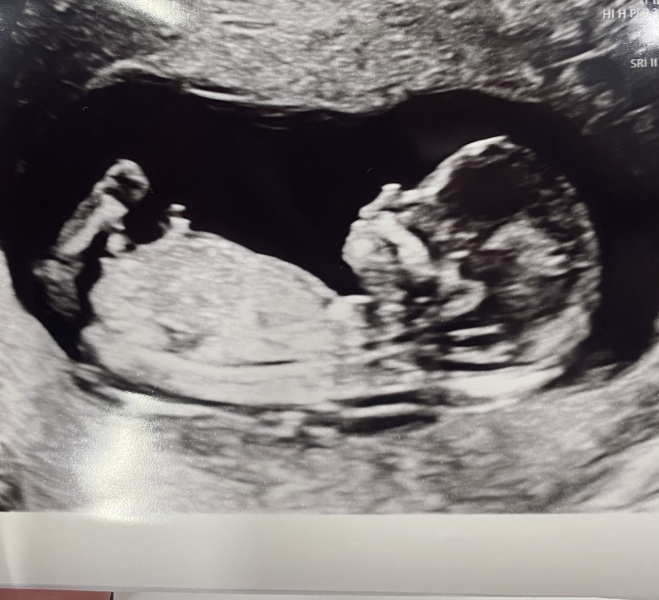

Have been too nervous to post before my 12 week scan, which I had today. Baby measuring a little further ahead than I thought at 13weeks, so I’m technically very end of Aug now but so sure I’ll go late so hoping you won’t kick me out as you all seem to lovely 🫣

@tryingfortwo2 what a lovely photo! My baby just wouldn't sit like that for us 😂he was upside down in a little corner, flat out refusing to give us a good pic 😂

All these scan pics are so lovely!

Ah love seeing the scan pics.